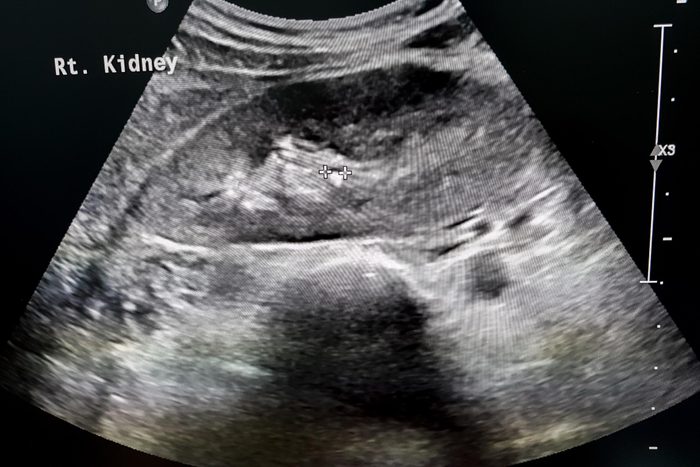

Ovarian cyst

This condition that happens only in women is characterized by lower abdominal pain during physical activity—including sexual intercourse. Ovarian cysts can occur naturally during the menstrual cycle in women of childbearing years. “When one of the small follicles that form on the surface of ovaries releases an egg, typically the cysts will shrink. But sometimes a normal cyst will not resolve but instead continue to grow to the point where it causes pain in the lower abdominal area,” explains Dr. Salsberry. “They are easily diagnosed with an ultrasound exam.” Sometimes a “wait and watch” approach is justified, as some abnormal cysts will eventually resolve on their own, says Dr. Salsberry; other times, hormonal treatment such as birth control pills may help. If your periods are irregular, polycystic ovarian syndrome (PCOS) should be ruled out; here are the most common signs of PCOS every woman should know.